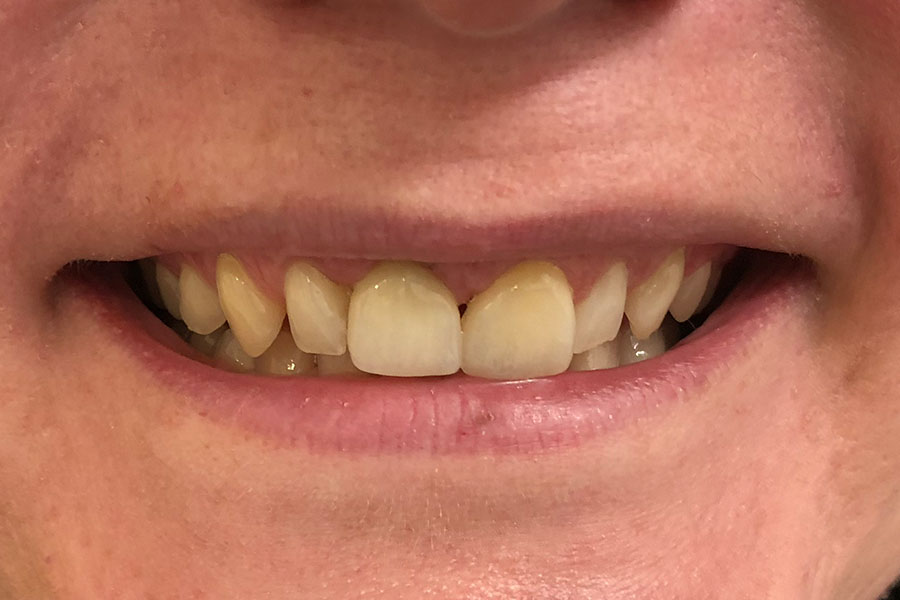

Andrew lost two front teeth while playing football about 40 years ago.

He wore a removable metal partial denture. These teeth were finally restored with two dental implants to support the teeth individually.